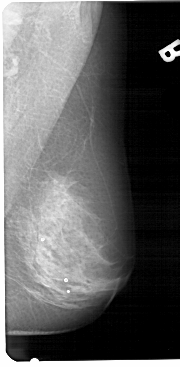

A_1316_1.LEFT_MLO

LEFT_MLO LINES 5491 PIXELS_PER_LINE 2731 BITS_PER_PIXEL 12 RESOLUTION 43.5 OVERLAY